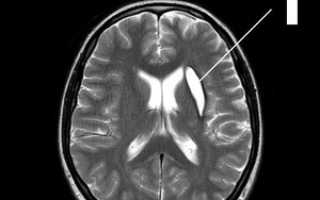

МР-томограммы мозга.1.     Киста после кровоизлияния в мозг2.    Кисты мозжечка после ишемического инсульта (закупорка мозговых артерий)3.     Кистозно-слипчивый арахноидит

Обследование и диагноз

МР-томография или КТ дадут однозначную информацию о наличии, размерах и расположении кисты. Отличить кисту от опухоли помогает исследование с внутривенным введением контраста: опухоль накапливает контраст, а киста – нет. Выполнить такое исследование Вы можете в Клинике Академии наук.

Чтобы избежать увеличения и появления новых кист, мы должны четко понимать и лечить первопричину их возникновения. Поэтому мы тщательно обследуем Вас на предмет нарушений кровообращения, инфекций, аутоиммунных заболеваний.